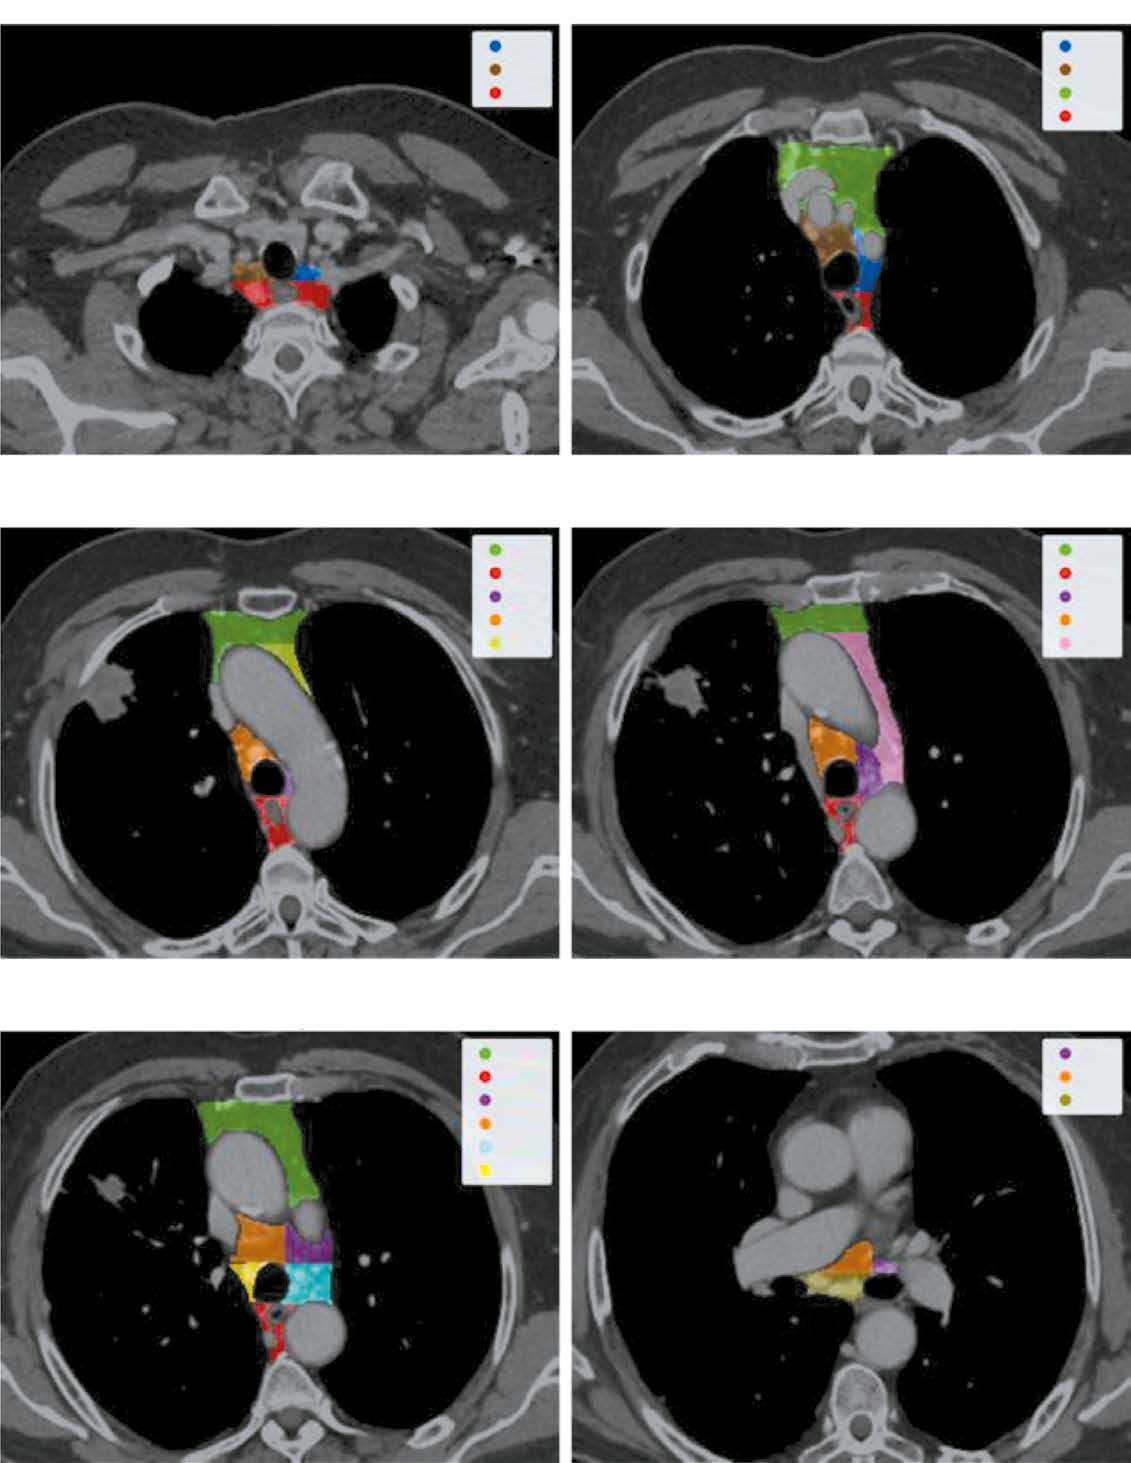

MATERIALS AND METHODS: Initially, IASLC lymph node stations are segmented, providing a bounding box of the mediastinum for further processing. Next, the image is cropped to this box and passed through a second network to identify and mask all visible lymph nodes. Finally, each detected lymph node is extracted, stacked with its mask, and evaluated by a feed-forward network to determine malignancy probabilities.